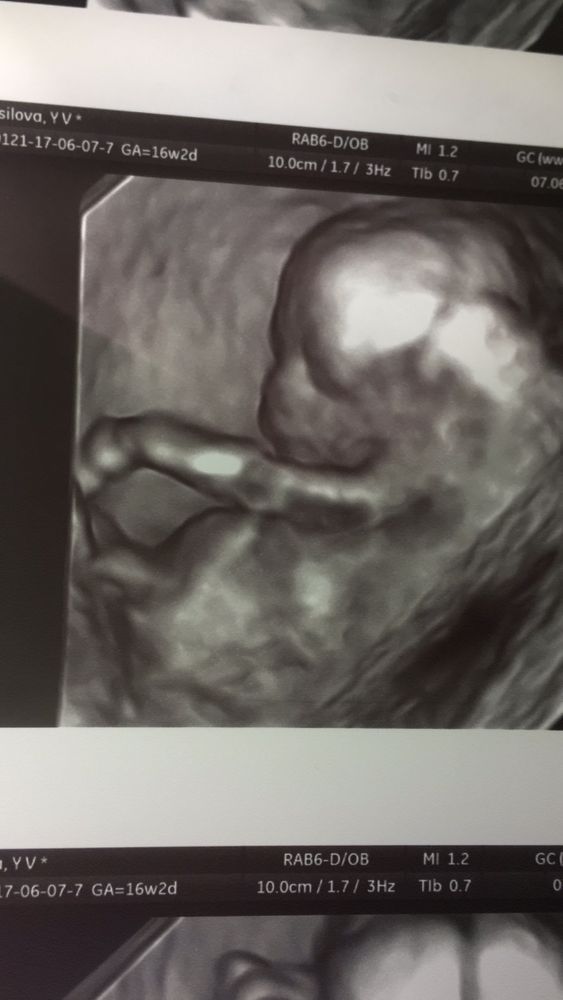

Я ходила узнать пол в 16.2, в 3 D сделать фото не вышло, дали обычную но как портрет. Может и зависит от оборудования. Позвоните уточните

Одно фото на 17 неделе, а второе на втором скрининге